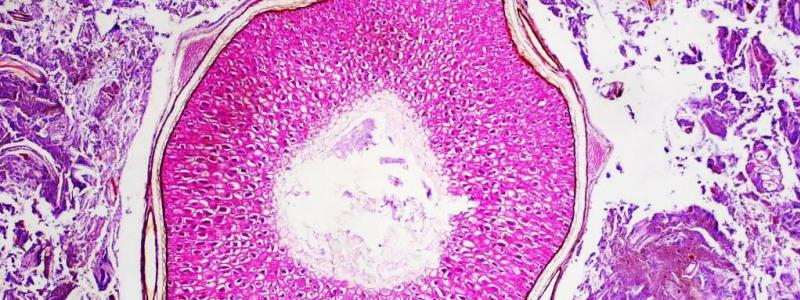

Patologicko-anatomické oddělení Pardubické nemocnice pořádá 2. krajský klinicko-patologický seminář nazvaný „Patologie napříč obory“.

Akce se uskuteční v pondělí 14. května 2018 od 13.00 hodin ve velké posluchárně Pardubické nemocnice (1. patro budovy č. 13 u hlavní vrátnice). „Budeme prezentovat zajímavé a často nelehké případy z bioptické diagnostiky, neobvyklou biopticko – nekroptickou kazuistiku a zajímavá sdělení si připraví i naši hosté,“ uvedla primářka pořádajícího oddělení MUDr. Mária Hácová. Na semináři vystoupí lékaři patologicko-anatomického oddělení Pardubické nemocnice. V programu se představí rovněž prof. MUDr. Václav Mandys, CSc. z Ústavu patologie 3. Lékařské fakulty Univerzity Karlovy a Fakultní nemocnice Královské Vinohrady a MUDr. Petra Kašparová, Ph.D. z Fingerlandova ústavu Fakultní nemocnice Hradec Králové.